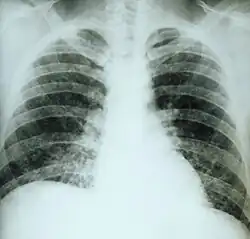

Chest X-ray of a patient with acute pulmonary histoplasmosis

Clinically, a wide spectrum of disease manifestations occurs, making diagnosis somewhat difficult. More severe forms include the chronic pulmonary form, often occurring in the presence of underlying pulmonary disease, and a disseminated form, which is characterized by the progressive spread of infection to extrapulmonary sites. Oral manifestations have been reported as the main complaint of the disseminated forms, leading the patient to seek treatment, whereas pulmonary symptoms in disseminated disease may be mild or even misinterpreted as flu.[21] Histoplasmosis can be diagnosed by samples containing the fungus taken from sputum (via bronchoalveolar lavage), blood, or infected organs. It can also be diagnosed by detection of antigens in blood or urine samples by ELISA or polymerase chain reaction. Antigens can cross-react with antigens of African histoplasmosis (caused by Histoplasma duboisii), blastomycosis, coccidioidomycosis, paracoccidioidomycosis, and talaromycosis infection. Histoplasmosis can also be diagnosed by a test for antibodies against Histoplasma in the blood. Histoplasma skin tests indicate whether someone has been exposed, but do not indicate whether they have the disease.[4] Formal histoplasmosis diagnoses are often confirmed only by culturing the fungus directly.[6] Sabouraud agar is an agar growth medium on which the fungus can be cultured. Cutaneous manifestations of disseminated disease are diverse and often present as a nondescript rash with systemic complaints. Diagnosis is best established by urine antigen testing, as blood cultures may take up to 6 weeks for diagnostic growth to occur and serum antigen testing often comes back with a false negative before 4 weeks of disseminated infection.[22]